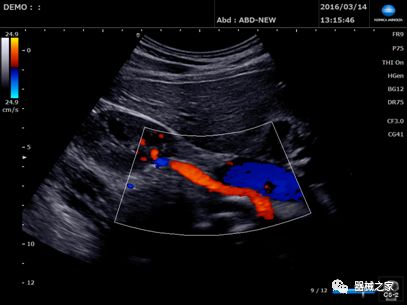

GE Healthcare用于胎儿超声的胎儿心脏和血管分析软件,在Voluson E10上提供,有助于在不到三分钟的时间内评估胎儿的心脏形状,大小和收缩性。称为辐射流的功能以三维视图显示血流。它还可以帮助显示缓慢流动的血液,例如神经血管循环。